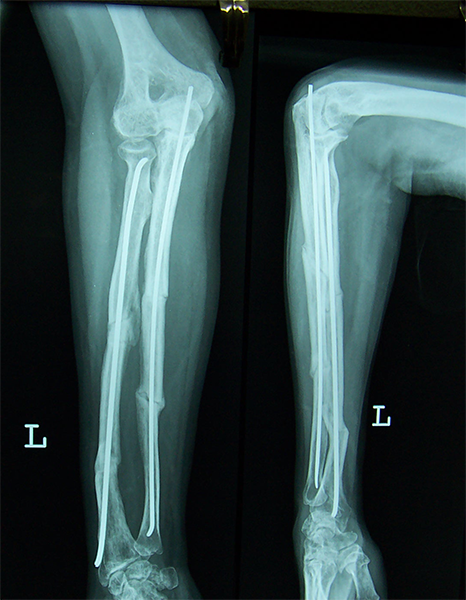

Case:6 Segmental Comminuted Fracture Radius

Patient, aged 75 years during morning walk tripped & had a fall following which he sustained injury to the left forearm. Closed reduction & interval fixation with Intra-medullary TEN nails was done in radius & ulna. Now he has full supination & pronation function of forearm.

Pre-Op

Post-Op

One and Half Months

3 Months Follow Up

4 Months Follow-Up